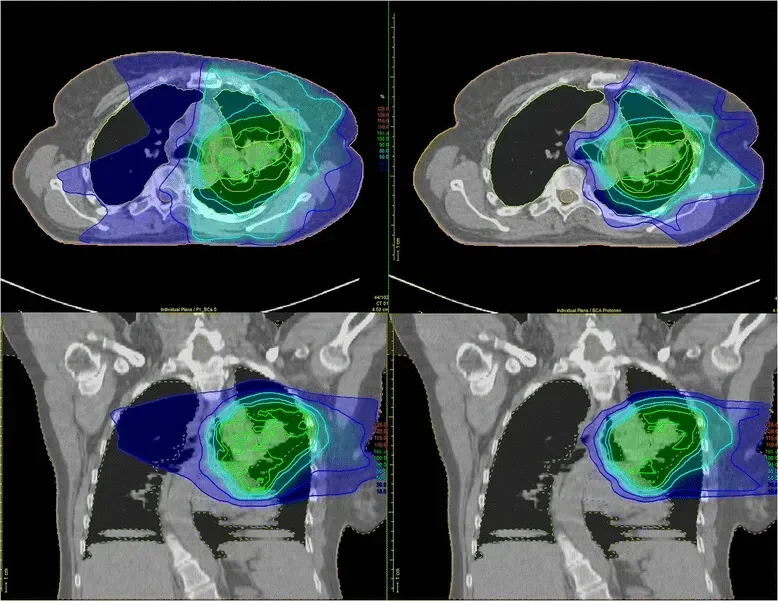

质子治疗则可将质子加速至约光速的三分之二,精准靶向肿瘤组织,大幅减少对周围健康组织与器官的辐射暴露,在有效治疗肿瘤的同时降低副作用、改善患者生活质量。从局部晚期非小细胞肺癌放疗对比图可见:传统调强放疗会将辐射波及肿瘤及周边健康组织;而质子治疗可将绝大部分能量集中于肿瘤区域,显著降低对重要危及器官的辐射剂量,更好地保护脏器功能。

▲图源“BMC”,版权归原作者所有,如无意中侵犯了知识产权,请联系我们删除